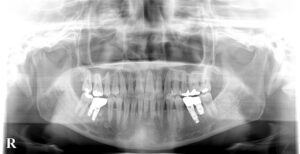

🔶初診のパノラマ🔶

しかし問題があり

上下の前歯は歯周病が進行し

矯正中にグラグラして抜けるリスクがあり

抜けた所は

インプラントを説明して

矯正開始